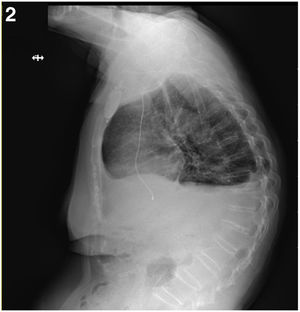

Caso clínicoPaciente mujer de 88 años con clínica de mareos recurrentes, de dos meses de evolución, que consulta a urgencias por episodio sincopal asociado a crisis convulsiva, donde tras la realización de estudios complementarios y nuevo episodio convulsivo presenciado, presenta asistolia por lo que son iniciadas maniobras de resucitación con recuperación posterior y desde el punto de vista electrocardiográfico desarrollando un bloqueo aurículo-ventricular completo transitorio, motivo que deriva su ingreso en cardiología para estudio electrofisiológico más extenso. Es entonces cuando tras la realización del traslado a su centro de referencia precisa la inserción de un marcapasos externo y de la administración de isoprenalina. A su llegada, se deriva a quirófano donde se realiza implante de marcapasos definitivo monocameral (VVI), con posterior mejoría, y traslado a planta de hospitalización convencional (figs. 1 y 2).